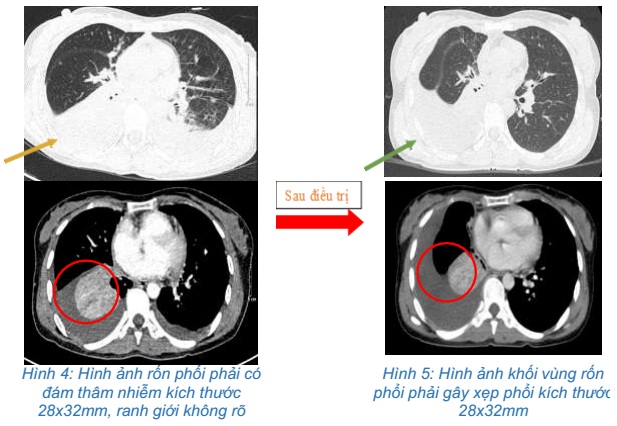

- Chụp cắt lớp vi tính ngực: Rốn phổi phải có đám thâm nhiễm kích thước 28x32mm, ranh giới không rõ, gây hẹp lòng và cắt cụt một số nhánh phế quản thùy dưới. Thùy trên phổi phải có nhiều nốt đặc, đám mờ kích thước lớn nhất 14x8mm. Dịch màng phổi hai bên, dày 28-30mm. Dịch màng ngoài tim dày 6mm. Thâm nhiễm mỡ lan tỏa trung thất, hạch trung thất kích thước lớn nhất 13x8mm.

Hình 1: Hình ảnh cắt lớp vi tính lồng ngực: Hình ảnh rốn phổi phải có đám thâm nhiễm kích thước 28x32mm

Hình ảnh dịch màng phổi hai bên, dày 28-30mm. Dịch màng ngoài tim dày 6mm. Thâm nhiễm mỡ lan tỏa trung thất, hạch trung thất kích thước lớn nhất 13x8mm

- Chụp cắt lớp vi tính ngực:Khối vùng rốn phổi phải gây xẹp phổi kích thước 28x32mm. Dịch khoang màng phổi phải dày 50mm. Khống thấy hạch to trung thất

So sánh hình ảnh cắt lớp vi tính ngực trước và sau điều trị 3 chu kỳ: